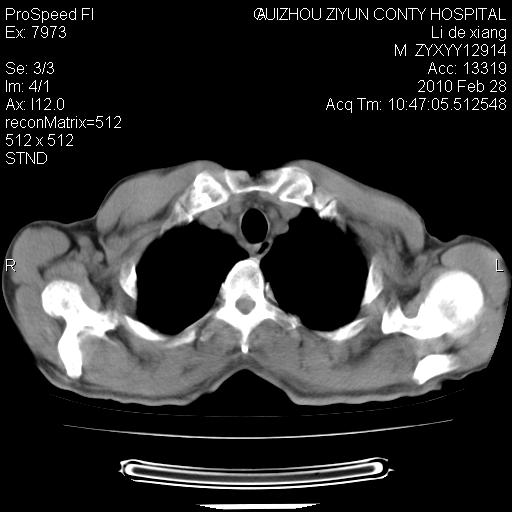

标题: CT24776:男 71Y 咳嗽咳痰胸痛两月,伴声音嘶哑。 [打印本页]

标题: CT24776:男 71Y 咳嗽咳痰胸痛两月,伴声音嘶哑。

纵膈淋巴结肿大 不除外占位性阻塞

左侧中央型肺癌伴左肺上叶阻塞性肺炎及节段性不张可能性大,建议纤支镜检查!纵隔淋巴结转移.

左上叶支气管狭窄,阻塞性病变,肺门肿块,纵隔及肺门淋巴结增大,中央性肺癌

左肺中央型肺癌并阻塞性改变、纵膈 淋巴结转移